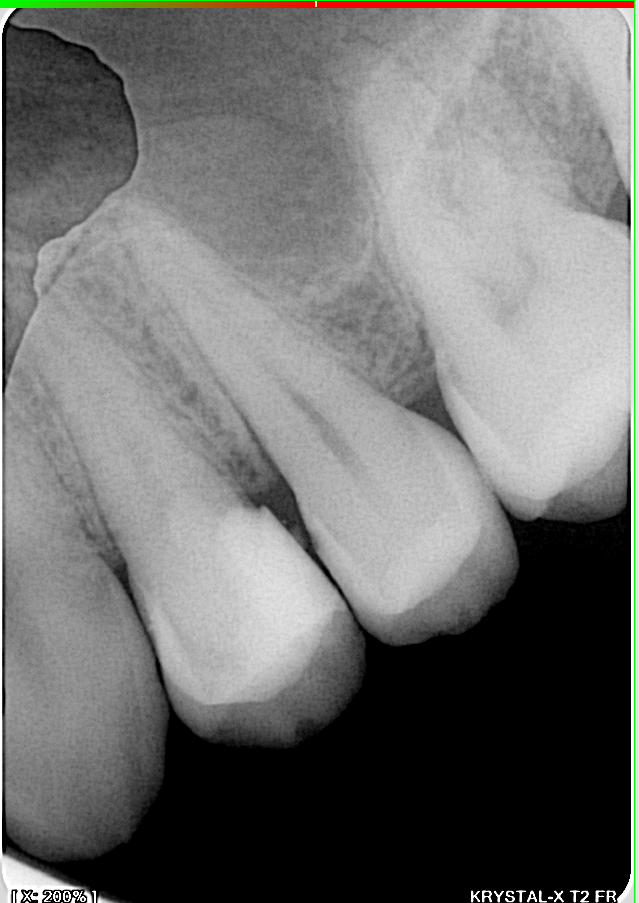

Preoperative radiograph: a significant decay is visible under the composite of the 1st premolar.